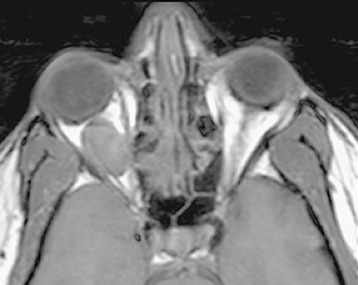

Figure 14.3.1: Axial T1-weighted image without fat suppression or gadolinium.

The vitreous is dark (hypointense) relative to the bright signal from fat. A well-circumscribed mass is clearly visible in the right orbit, also hypointense. Most orbital lesions are dark in T1 prior to gadolinium injection. The notable exceptions are listed in Table 14.3.2.